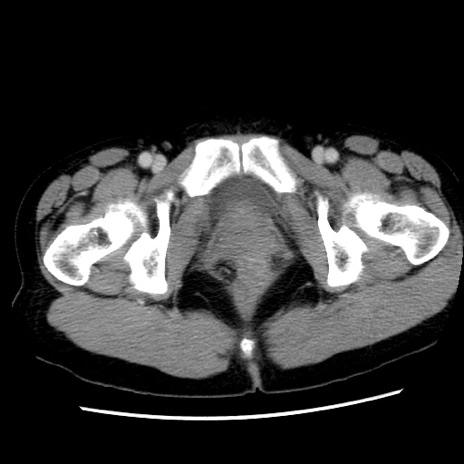

症例10(横断像)

【症例】 50歳代女性

【主訴】 腹痛

【現病歴】前日生レバーを食べた。今朝に排便あり。 昼前に突然発症の腹痛を生じ、当院救急外来を受診した。

【既往歴】 子宮筋腫にてで子宮全摘後

【身体所見】 意識清明、腹部:平坦、軟、下腹部やや左を中心に圧痛・反跳痛あり、筋性防御あり

【データ】WBC 7800、CRP 0.07